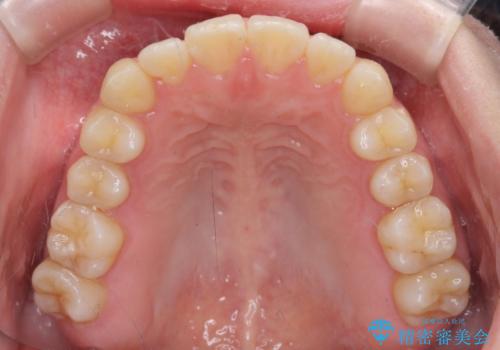

- ちょっとしたデコボコを整えたいとのことで来院された患者様です。

歯列不正は軽微であったため、インビザライン・ライトにより、費用を抑えて矯正治療を行うこととしました。

上下前歯の捻れが改善され、患者様には大変満足していただきました。